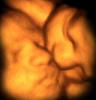

A crowded womb

Daily MailJan 16

A twin leans over and kisses the cheek of her sister in a heart-warming picture that would not be out of place in any family home.

Yet these siblings are a not even born and the astonishing images have been captured on a new 'four-dimensional' ultrasound scan of the womb.

The scans are a highly developed form of traditional ultrasound where very high frequency sound waves are used to produce images of what is inside the body.